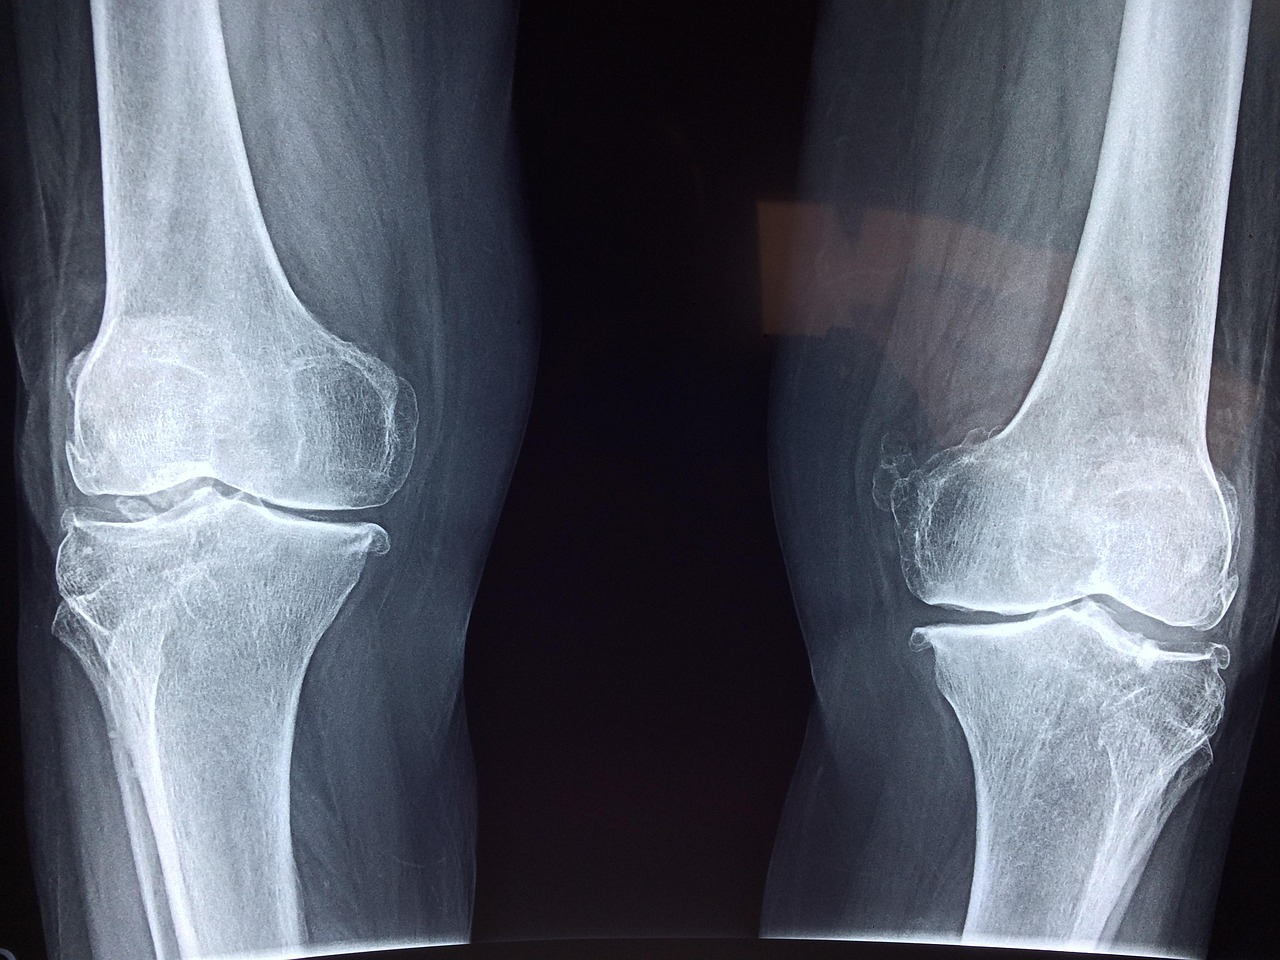

In addition to exercise, maintaining a healthy weight is crucial for protecting your joints. Excess weight can put significant strain on load-bearing joints, such as the knees and hips. A balanced diet rich in fruits, vegetables, lean proteins, and whole grains can assist in achieving and maintaining a healthy weight. Reducing the intake of processed foods high in sugar and saturated fats can also decrease inflammation, benefiting joint health. Regularly monitoring caloric intake may further help in managing weight effectively. Portion control may be essential in preventing overeating. Moreover, consider consulting a dietitian to craft a personalized nutrition plan suited to your needs. Engaging in mindful eating practices can promote a positive relationship with food, while also supporting your wellness goals. Aim to implement regular physical activity into your routine without overcommitting, ensuring sustainability. Simple changes like taking the stairs instead of the elevator can make a considerable difference over time. Prioritizing healthy habits in your lifestyle can lead to improved joint health and overall wellness, making activities more enjoyable and less painful long-term.